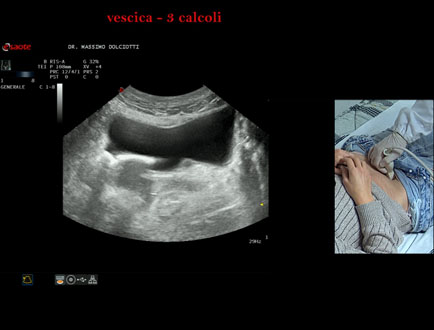

Data inserimento: 21/10/2025

Ecografia del: 15/10/2025

Strumento: Esaote MyLab Eight

Sonda: Convex Multifrequenza 1-8 MHz

Età Paziente: F 45 anni

Motivazione dell'esame: da alcuni mesi, disuria ed infezioni urinarie recidivanti.

Commento all'esame: le immagini ed il video documentano 3 immagini iperecogene, con cono d'ombra posteriore, da ricondurre a litiasi multipla della vescica.

Conclusioni: 3 calcoli della vescica (3 bladder stones).

Presentazione: Dr. Massimo Dolciotti - Ancona

Elaborazione digitale: Andrea Dini - Ancona